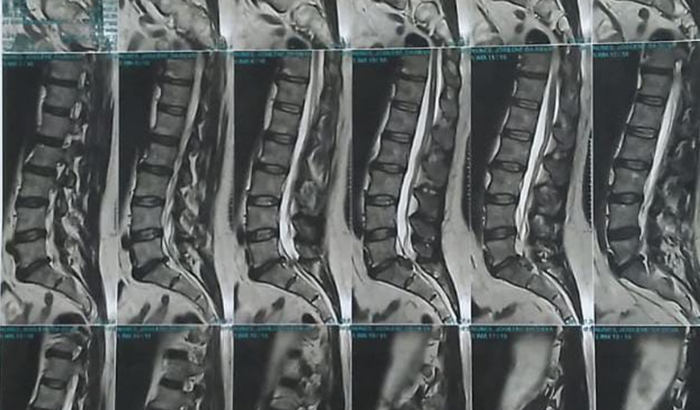

Oi! Me chamo Josilene e fiz essa vakinha no valor de R$30.000,00 , porque preciso fazer uma cirurgia na coluna urgente, estou com uma hernia de disco gigantesca e o médico solicitou cirurgia, devido eu estar a mais de 30 dias de cama sem conseguir levantar, sinto minha perna e pé esquerdo dormente. A seguir irei contar mais detalhes sobre meu diagnóstico.Comecei sentir dores muitos fortes na perna, fui até CIS e encaminharam de ambulância para o hospital Marieta para fazer ressonância pois suspeitavam de fratura na vértebra, pois fui medicada com Morfina e a dor não passava, porém ao chegar no hospital o médico mandou eu vir pra casa e procurar o posto de saúde pra solicitar encaminhamento pra ressonância, como já sabem SUS leva meses para ser chamado pra realizar esse tipo de exame , então minha família se reuniu e arcou com custos da ressonância, desde então tive o diagnóstico da hernia que é muito grande e que está comprimindo o nervo da minha perna esquerda me impossibilitando de caminhar , estou de cama a 30 dias e nada é resolvido. Realizei várias tentativas de atendimento no hospital Marieta pois o médico informou que era urgente realizar a cirurgia, porém eles só medicaram e mandaram pra casa e e orientaram dar entrada para solicitar uma fisioterapia, já estava saturada de ir e voltar do hospital e nada ser feito.No dia 21 realizei uma consulta com um ortopedista especialista da coluna , e me informou que não tem o que fazer há não ser cirurgia, como ja tentamos no Sus e não querem realizar a cirurgia, optamos por pagar a cirurgia particular, pois eu tinha uma vida normal e desde então meus dias estão sendo em cima de uma cama, sem conseguir andar.